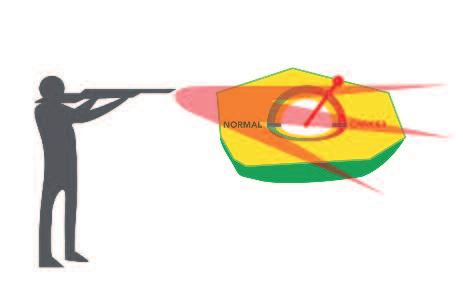

l'obiettivo terapeutico della chemioterapia e della radioterapia è quello di uccidere le cellule tumorali intossicando tutto il corpo

La radioterapia e la chemioterapia, utilizzate dalla medicina convenzionale fino ad oggi per combattere il cancro, hanno un comune effetto ‘terapeutico’: assieme alle cellule tumorali uccidono anche miliardi di cellule sane. Queste procedure altamente tossiche danneggiano indiscriminatamente tutte le cellule del corpo dei pazienti e sono, quindi, terapie “non selettive” sulle cellule cancerogene.

A peggiorare le cose, la chemioterapia colpisce in particolare le cellule sane del nostro corpo che si moltiplicano rapidamente, ad esempio i globuli bianchi del sistema immunitario. Così, quando il corpo di un malato di cancro ha maggiore necessità di una difesa efficace, le cellule immunitarie vengono sistematicamente distrutte da questi farmaci molto tossici.

Anche un profano può capire che se la medicina deve ricorrere ad una terapia non selettiva, ciò sta ad indicare solo una cosa: le cause e i decorsi della malattia non sono propriamente compresi, quindi non possono essere definite terapie efficaci che agiscono specificamente sulle cellule tumorali.

Per ingannare i pazienti e fornire false speranze, la medicina convenzionale utilizza i termini ‘chemio-terapia’ e ‘radio-terapia’, quando in realtà non esiste nessuna ‘terapia’ efficace. L’uso della terapia convenzionale contro il cancro degli ultimi decenni può essere definito come un fallimento della medicina.

Radiote rapi a e chemi ot erapia uc cidono le ce llul e tumoral i e anc he l e cel lule s ane.

Gli approcci terapeutici dominanti per questa malattia da parte della medicina convenzionale (la chemioterapia e la radioterapia) sono basati sul danneggiamento e sull'uccisione indiscriminata di miliardi di cellule del corpo nella speranza di eliminare il cancro.

Le statistiche dimostrano come questo approccio di ‘intossicazione’ sia un fallimento. Per molti tipi di cancro, la chemioterapia e la radioterapia non presentano alcun vantaggio, per altri tipi di tumore gli effetti sono stati minimi, a breve termine, e sono stati ottenuti attraverso sofferenze e un drastico calo della qualità della vita del paziente.

Chemioterapia

Radiazioni